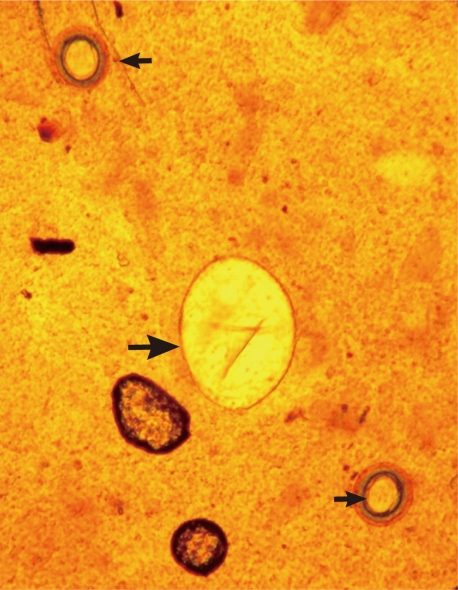

Fig. 2) and two round or slightly lobated testes. The eggs (

Figs. 3,

4) were 94 µm long (89-99 µm) and 55 µm wide (52-58 µm) (n=10), and had a relatively wide, somewhat inconspicuous operculum, a thin and refractile shell, and abopercular wrinkles terminally. In Kato Katz fecal smears, the operculum and abopercular wrinkles of the eggs are less apparently seen (

Fig. 4).

Fig. 3An Echinostoma ilocanum egg (99×56 µm; larger arrow) and 2 Taenia sp. eggs (small arrows) detected in a Kato-Katz fecal smear of a patient. ×200.

Fig. 4Another E. ilocanum egg (102×58 µm) found in a Kato-Katz fecal smear of a patient. Note the thin and inconspicuous operculum (arrow; up) and a tiny abopercular knob at its terminal end (arrow; down). ×400.